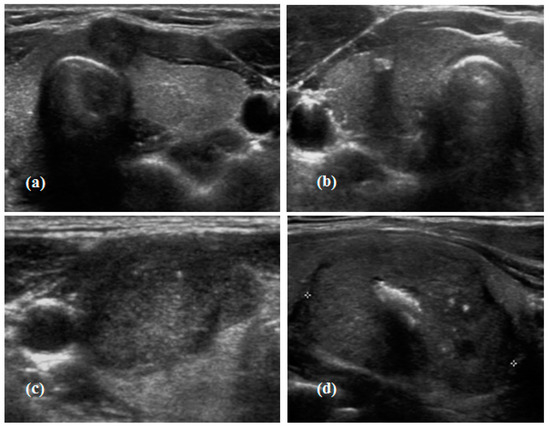

2.3. Calcification Pattern in Thyroid Cancer

- Shin, J.H.; Baek, J.H.; Chung, J.; Ha, E.J.; Kim, J.H.; Lee, Y.H.; Lim, H.K.; Moon, W.J.; Na, D.G.; Park, J.S.; et al. Ultrasonography diagnosis and imaging-based management of thyroid nodules: Revised korean society of thyroid radiology consensus statement and recommendations. Korean J. Radiol. 2016, 17, 370–395. [Google Scholar] [CrossRef] [PubMed]